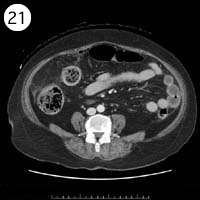

57歳 女性

単純CT

造影CT